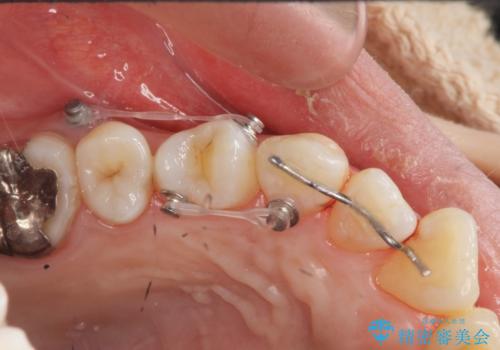

捻れた奥歯 突き出た前歯を治したい

- インビザライン +部分ワイヤー矯正

- 出っ歯に見える前歯、捻れてしまった小臼歯の改善を求めて来院されました。

マウスピースでは改善の難しい小臼歯のねじれをまず部分ワイヤー矯正で改善し、その後マウスピース矯正で前歯の突出感を改善します。